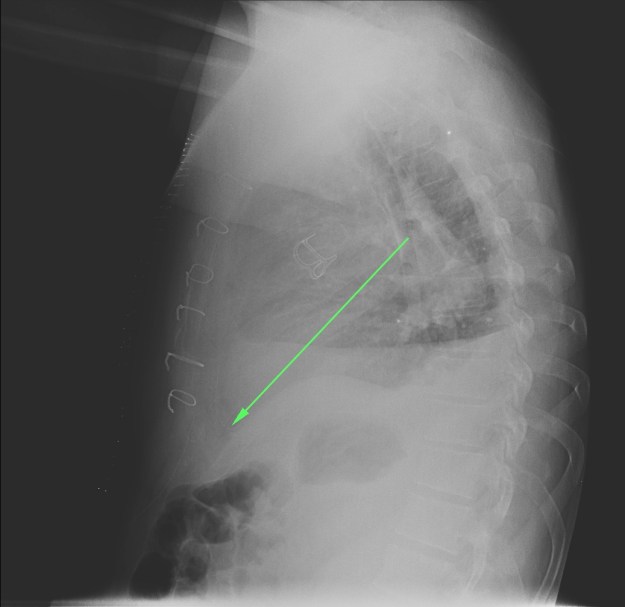

CASO: Febrícula y tos de 4 días de evolución.

Hallazgos:

- En la placa PA se observa una asimetría en los hilios pulmonares, el hilio izquierdo tiene una densidad aumentada.

- Tras examinar la placa lateral se observa un aumento de densidad en la columna que puede ser compatible con una condensación, es el signo de la desnificación vertebral.

SIGNO DE LA DENSIFICACIÓN VERTEBRAL: En la radiografía lateral normal, la densidad de la columna torácica tiende a disminuir desde la parte superior hasta el diafragma; la alteración de ese patrón por la presencia de una densidad superpuesta a la columna, indica la existencia de una consolidación pulmonar. Este signo adquiere especial valor cuando en la proyección posteroanterior la consolidación está oculta en el espacio retrocardíaco o en la base pulmonar.